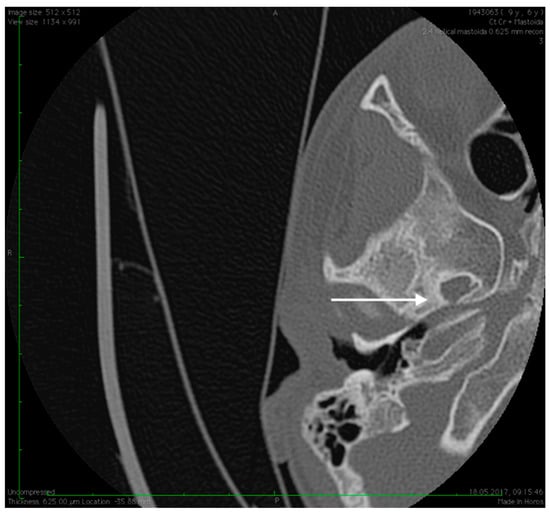

Figure 6.

Abnormal position of the facial nerves in their mastoid segment, bilaterally (arrows).

No family history of hearing problems could be elicited. A high resolution CT scan revealed bilateral middle ear anomalies. There were no images of the oval window and stapes suprastructure in his left ear, with abnormal facial nerve canal position and patent foramen spinosum (Figure 2 and Figure 3). The stapes suprastructure and the oval window were also missing to the contralateral (right) ear with a wide facial nerve canal between the geniculate and the round window niche and an abnormal traject on its mastoid segment. No foramen spinosum was observable on the right side (Figure 4, Figure 5 and Figure 6). Furthermore, surgery was carefully planned to investigate the middle ear.